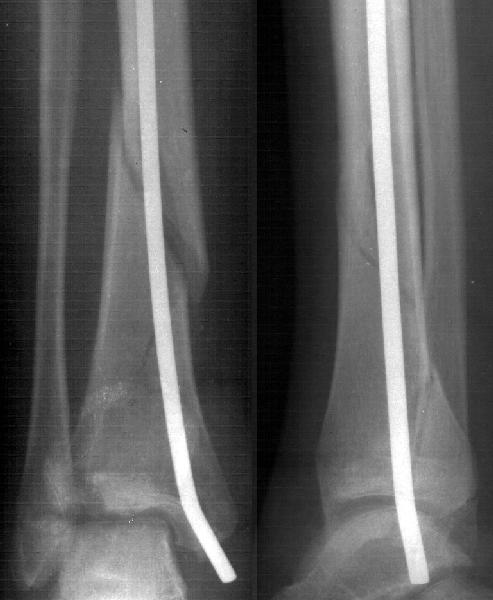

Девочка 14 лет полтора года назад оперирована в детской больнице по поводу спирального перелома костей голени (снимок 1)- выполнен закрытый остеосинтез стержнем Богданова, введенным ретроградно с медиальной стороны (снимок 2). Фиксатор после сращения удален

(см. снимки 3 и 4, после удаления, для сравнения со здоровой стороной, фас - стоя с нагрузкой на обе ноги). В настоящее время беспокоят боль и отеки в области голеностопного сустава при нагрузках, после ходьбы. В покое и ночью боли нет.Амплитуда движений в голеностопном суставе практически полная. Имеется заметная боковая нестабильность, т.е. несостоятельность дельтовидной связки и межберцоого синдесмоза. Складывается впечатление, что при остеосинтезе был отколот и смещен в сторону сустава костный фрагмент позади внутренней лодыжки, увеличилось смещение отломка заднего края, что привело к столь ранним проявлениям деформирующего артроза. Встает вопрос - что делать сейчас?Артодез - наверно, рано. Ревизию сустава, моделирующую резекцию?Пластику связок? Что-то еще? Заранее спасибо.